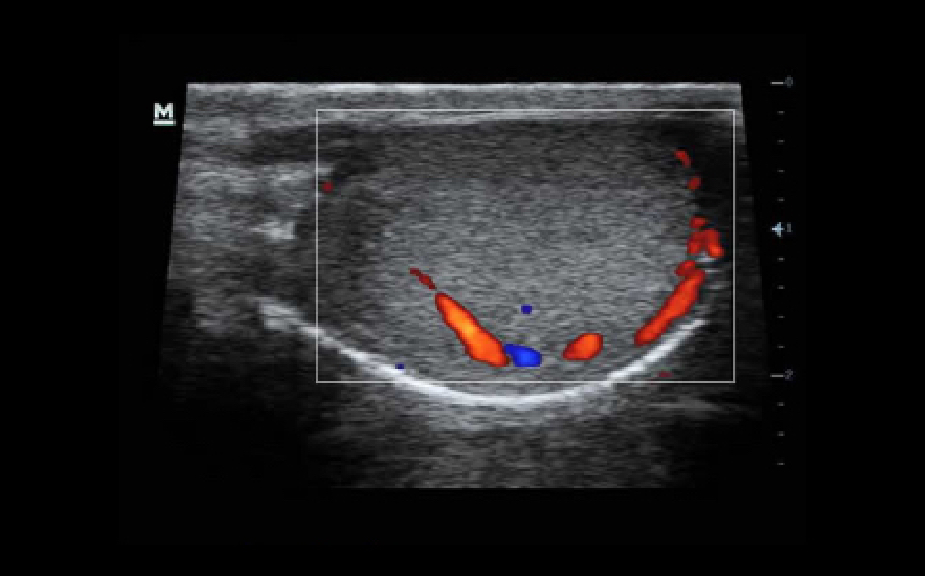

PSH? (Phase Shift Harmonic Imaging)

ImĂĄgenes de armĂłnicos purificados con desplazamiento de fase para una mejor resoluciĂłn de contrastes que proporciona imĂĄgenes mĂĄs nĂtidas con excelente resoluciĂłn y menos ruido.

iBeam?

Permite el uso de varios ĂĄngulos de exploraciĂłn para formar una sola imagen, lo que ofrece una mayor resoluciĂłn de contrastes y una mejor visualizaciĂłn.

iClear?

Mejor calidad de imagen basada en la detecciĂłn automĂĄtica de estructuras.

- Bordes mĂĄs nĂtidos y continuos

- Tejidos uniformes lisos

- â?reas sin ecoâ mĂĄs limpias